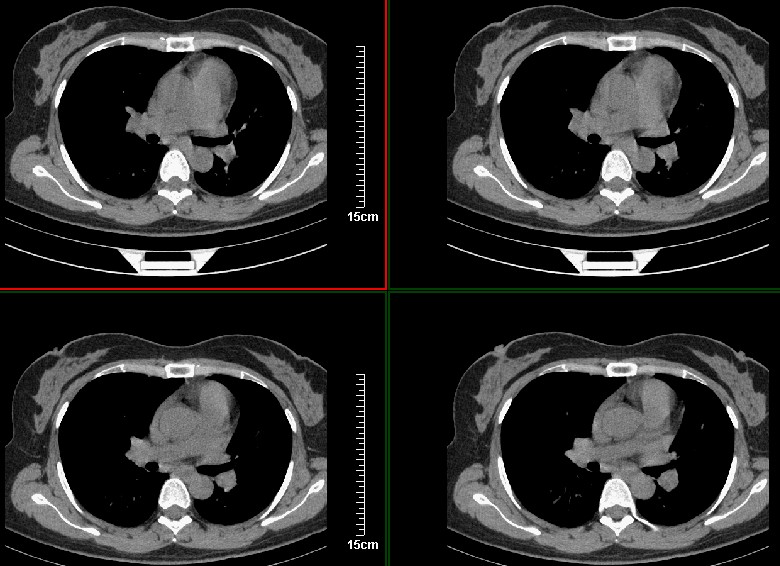

一周之后 复查结果 5mm扫描 40多岁 我们医院的护士

左上肺周围型肺癌可能性大,楼主片子太小

第八幅图像,典型毛刺,像日本鬼子的膏药军旗一样,一看就不是个好东西

左肺上叶肿块,肺窗周围有“晕征”,纵隔窗有毛刺,临床资料???只能考虑占位???